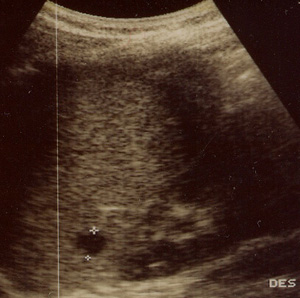

L'ecografia dell'addome dimostra a livello del polo superiore della milza immagine ipoecogena di diametro 8 mm senza rinforzo posteriore, riferito a micro ascesso splenico compatibile con granulomatosi splenica.

Una particolare forma sistemica di malattia da graffio di gatto è quella denominata granulomatosi epato-splenica multifocale caratterizzata da presenza di lesioni focali ipoecogene con diametro compreso tra 8 e 20 mm. a livello epatico e/o splenico,con normalità dei parametri di citolisi epatica. Queste lesioni evolvono verso la guarigione con totale scomparsa o con calcificazioni residue nel giro di 5-6 mesi.